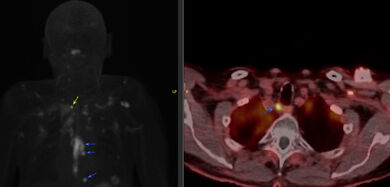

Abbildung: Links Projektion der PET-Avidität mit Markierung des Speiseröhrenkrebses (oberer blauer Pfeil) und Lymphknotenmetastasen (untere zwei blaue Pfeile). Der gelbe Pfeil im linken Bild zeigt die deutlich weiter kopfwärts aufgefallene Lymphknotenmetastase, rechts in der Fusion mit der CT dargestellt. Die differenzierte Ausbreitungsdiagnostik soll dabei unterstützen, die gesamte Tumorausdehnung während einer Strahlentherapie oder Operation zu berücksichtigen.